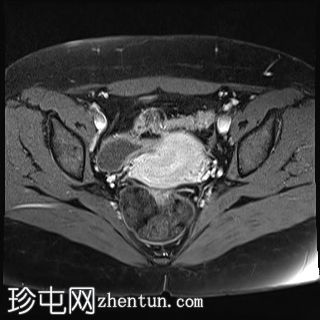

轴位

T2加权像

双侧卵巢位置接近(卵巢相吻),左侧卵巢内可见一边界清晰的囊性病变,大小约3.1 × 2.7 × 2.9 cm,T1加权像呈高信号,T2加权像可见暗点征及内部暗点征。以上MRI特征符合卵巢子宫内膜异位囊肿的诊断。

右侧卵巢可见一囊肿,大小约为 2.8 × 2.0 × 2.2 cm,T1 加权像呈高信号,囊内可见液-液平面,提示囊内含有不同时期的出血性物质。由于对侧卵巢存在典型的子宫内膜异位囊肿,且该囊肿无强化,影像学表现强烈提示为另一子宫内膜异位囊肿。

双侧卵巢均可见多个小卵泡。